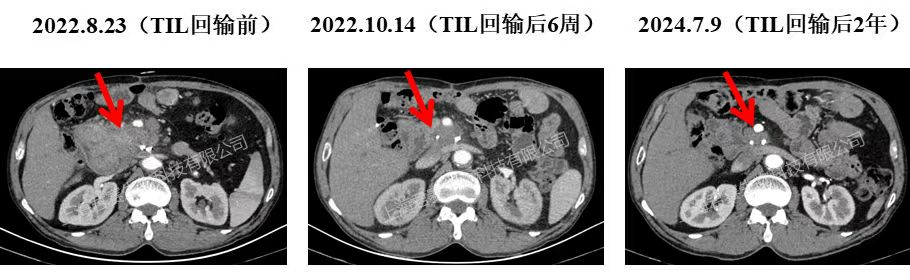

除了黑色素瘤外,GC101在胰腺癌治疗中也获积极进展,君赛生物曾报道过一例“GC101治疗晚期胰腺癌”的振奋案例:该患者是一位晚期胰腺癌男性,术后复发伴肝转移,入组GC101临床试验后,单次回输TIL细胞6周,结果显示:胰头复发病灶从10cm缩至3cm,肝转移病灶完全消失(详见下图),肿瘤标记物恢复正常,截至目前已正常生活超39个月。

▲图源“JUNCELL”,版权归原作者所有,如无意中侵犯了知识产权,请联系我们删除